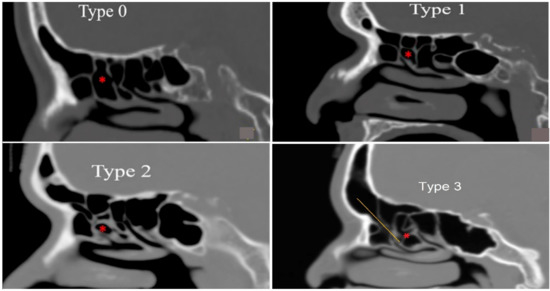

- Type 0 was absent of suprabullar air cells between ethmoid bulla and skull base;

- Type 1 was presence of a single suprabullar air cell between ethmoid bulla and skull base;

- Type 2 was presence of multiple suprabullar air cells above the ethmoid bulla, without extension into the frontal sinus;

- Type 3 was presence of either a single or multiple suprabullar air cells above the ethmoid bulla, with extension into the frontal sinus;